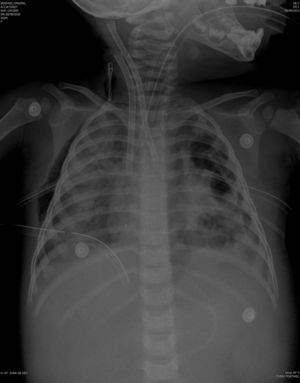

The previously started inotropic therapy was maintained, and a steroid treatment for relative suprarenal insufficiency in the context of septic shock was started. Other treatments were sedation with fentanyl and midazolam, neuromuscular blockade and parenteral nutrition with gastric protection. Fig. 1 shows radiologic examination at the time of starting ECMO.